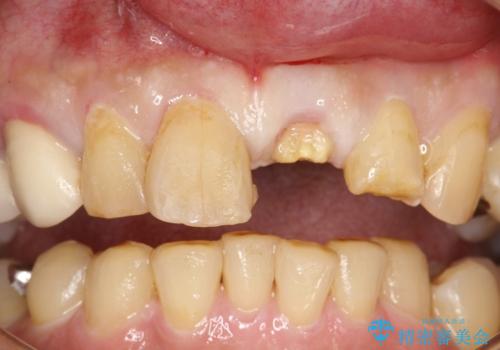

- 左の前歯で硬いものを咬んだら、歯からバキッと音がしてその衝撃で痛みが出た、その後前歯がゆれると来院されました。

左上1が水平的に割れている状態で、歯冠を取り除くと神経が露出しており、唇側はかなり歯肉縁下で破折しており、そのままではかぶせものを入れるのは難しい状態でした。

抜かずになるべくその歯を残して使っていきたいとのことで、